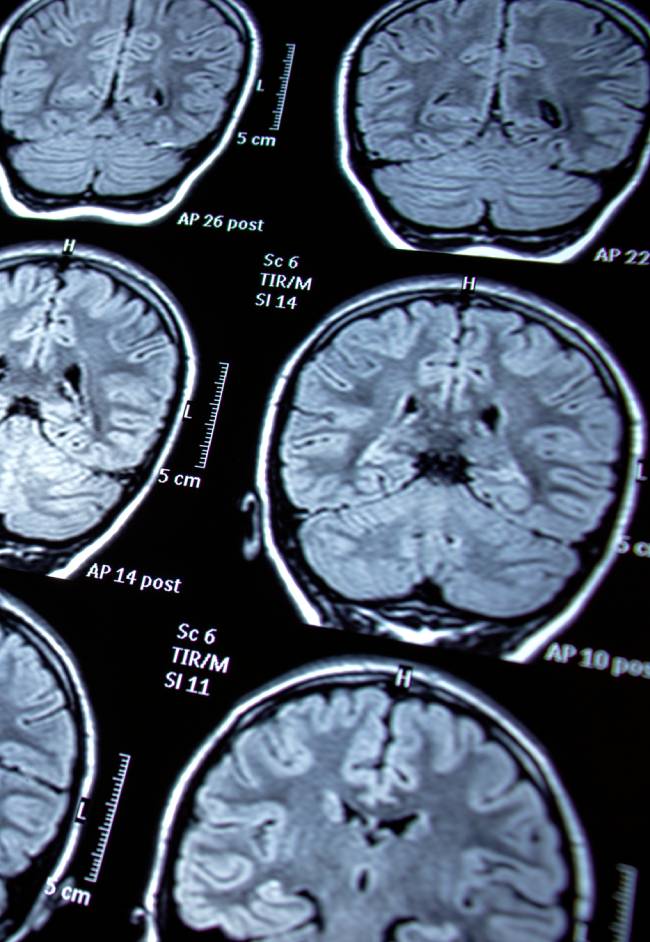

Trigeminal neuralgia is a chronic pain condition affecting the trigeminal nerve, which carries sensation from the face to the brain. It causes sudden, severe, electric shock-like facial pain, often triggered by simple actions like chewing, speaking, or touching the face. Episodes can last seconds to minutes and may occur in clusters. The condition is often caused by blood vessel compression of the nerve, but can also result from multiple sclerosis or nerve injury.

Initial treatment typically includes medications to stabilize nerve activity. For patients who do not respond to medication, surgical options such as microvascular decompression, radiosurgery, or percutaneous procedures can provide long-term relief. Dr. Sarkiss will fully evaluate your medical history and situation to provide appropriate recommendations and care.